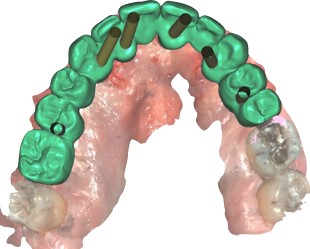

Réalisation de prothèses par informatique

Les données numériques issues des empreintes et de la planification sont ensuite utilisées pour fabriquer des prothèses personnalisées avec une précision micrométrique. Les technologies de fabrication assistée par ordinateur (FAO) permettent de produire des prothèses de haute qualité, parfaitement ajustées, réduisant ainsi le temps d’ajustement et augmentant le confort du patient.